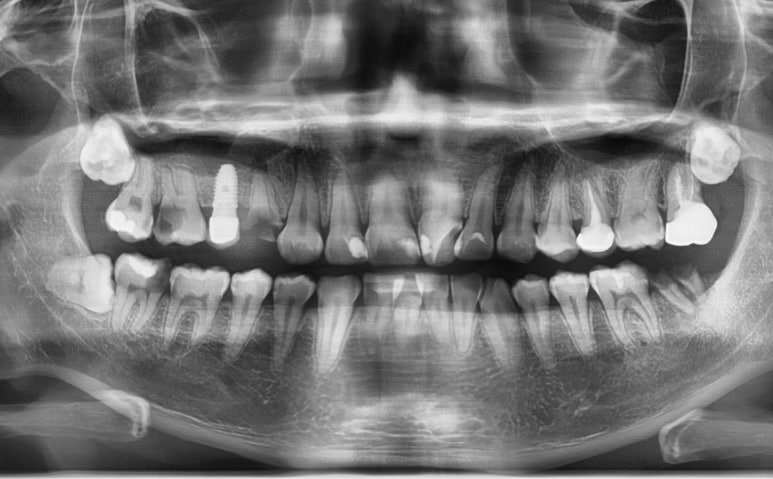

충치치료의 검진

충치검진에 엑스레이 사진은 필수입니다.

치아는 겉에서부터 썩는 경우도 있지만

속에서 썩어있는 경우도 많기 때문입니다.

겉에서 멀쩡하고 속에서 썩은 경우가 더 문제가 될 확률이 많습니다.

겉에서 보는 검진만 하고 엑스레이를 찍지 않는다면 수박겉핥기식 검진이 될 수 있겠죠.

그래서 먼저 충치검진을 하러오면 전반적으로 보는 파노라마 엑스레이와 치과의사선생님의 시진을 하게됩니다.